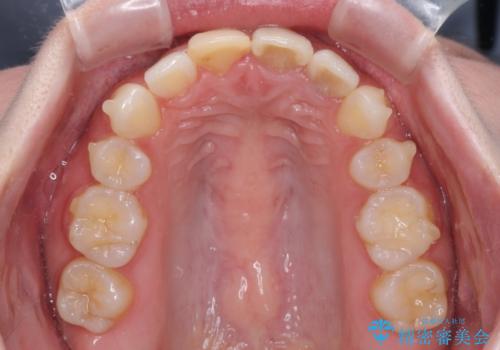

抜歯矯正の後戻り インビザラインによるオープンバイトの再矯正

- 以前矯正治療をされていましたが、後戻りが起きたことを気にして来院された患者様です。

上下前歯のオープンバイトを改善するため、インビザラインにて治療を行うこととしました。

外食が楽しみである患者様だったので、インビザラインによる治療期間は我慢の時期であったようです。

自己管理を徹底していただいたので、1年程度で治療を終えることができました。